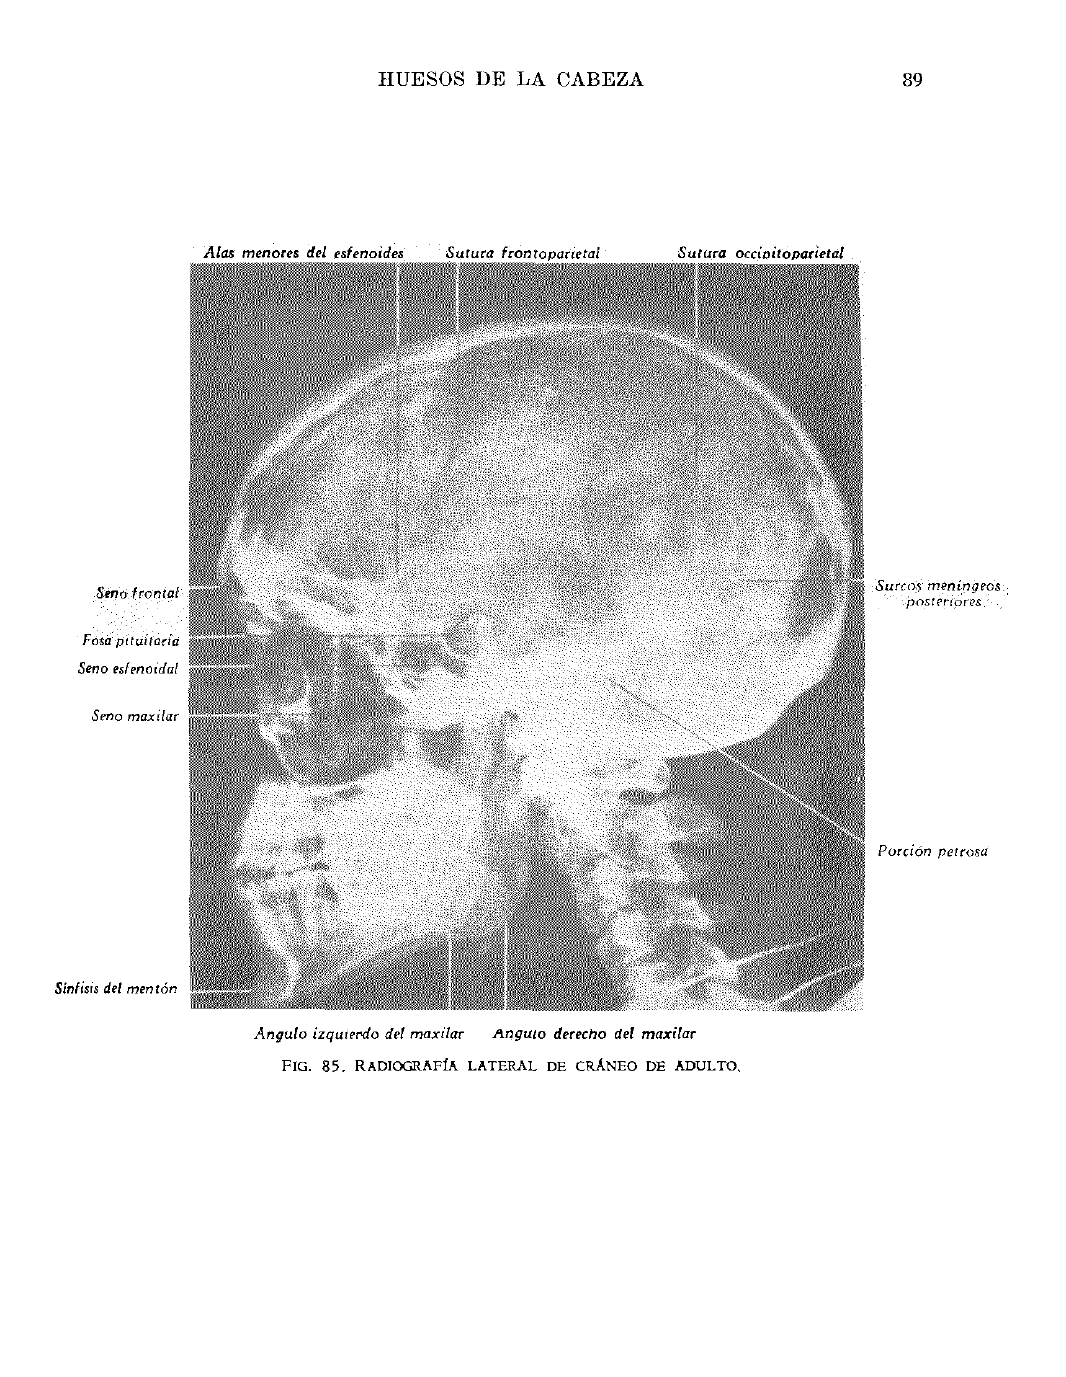

A la s m en ores del esfenoides S u tu r a f r o n i o p a n e t a i S u tu r a o cc io i to p a r ie ta l

Seno fronta l

Fosa p itu itaria

Seno esfenoida!

Seno maxilar

S u rc o s m e n ín g eo s

po s ter io res

P o rc ió n p e tro sa

Sínfisis del m en tón

A n g u l o i z q u ie r d o de l m a x i la r A n g u l o derecho de l m a x i la r

F ig . 8 5 . R a d io g r a f ía l a t e r a l d e c r á n e o d e a d u l t o .